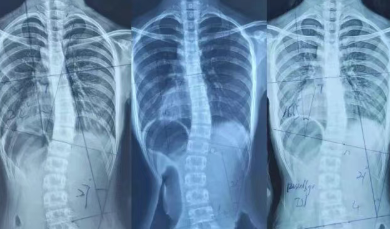

脊柱健康与人的“精气神”有着千丝万缕、至关重要的联系。它不仅仅是支撑身体的“柱子”,更是能量、信息和气质的中枢通道。<img src="/p/weixin-mpimg-get.html?id=0&fid=12&url=http%3A%2F%2Fmmbiz.qpic.cn%2Fsz_m..